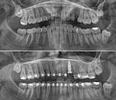

وأكمل دراسته الجامعية في كلية طب الأسنان بجامعة إسطنبول (تشابا ديش) عام 2010. خلال سنوات الجامعة كتب أطروحته حول "الأدوية المستخدمة في علاج قنوات الجذر في العلاجات الإندودونتيكية". أتم فترة تدريبه كمعيد في قسم تقويم الأسنان في كلية طب الأسنان بجامعة أتاتورك، ودافع بنجاح عن أطروحته التي حملت عنوان 'المقارنة بين التأثيرات الدنتوفاسيالية والجمالية لنظام تثبيت الميني-براغي وأنظمة تقويم الأسنان التقليدية لإنقاص بروز القواطع لدى مرضى العضّة العميقة'، ونال لقب دكتور في تقويم الأسنان (دكتوراه).

تقويم الأسنان